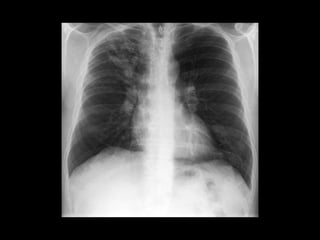

ASPERGILOSIS CRÓNICA NECROTIZANTE

• Necrosis e inflamación granulomatosa.

• DM, malnutrición, alcoholismo, uso crónico de

corticoesteroides y EPOC.

• Tos crónica, esputo, fiebre y síntomas constitucionales.

ASPERGILOSIS CRÓNICA NECROTIZANTE •Necrosis e inflamación granulomatosa. • DM, malnutrición, alcoholismo, uso crónico de corticoesteroides y EPOC. • Tos crónica, esputo, fiebre y síntomas constitucionales. Spectrum of Pulmonary Aspergillosis: Histologic, Clinical, and Radiologic Findings Tomás Franquet, Nestor L. Müller, Ana Giménez, Pedro Guembe, Jesus de la Torre, and S. Bagué RadioGraphics 2001 21:4, 825-837